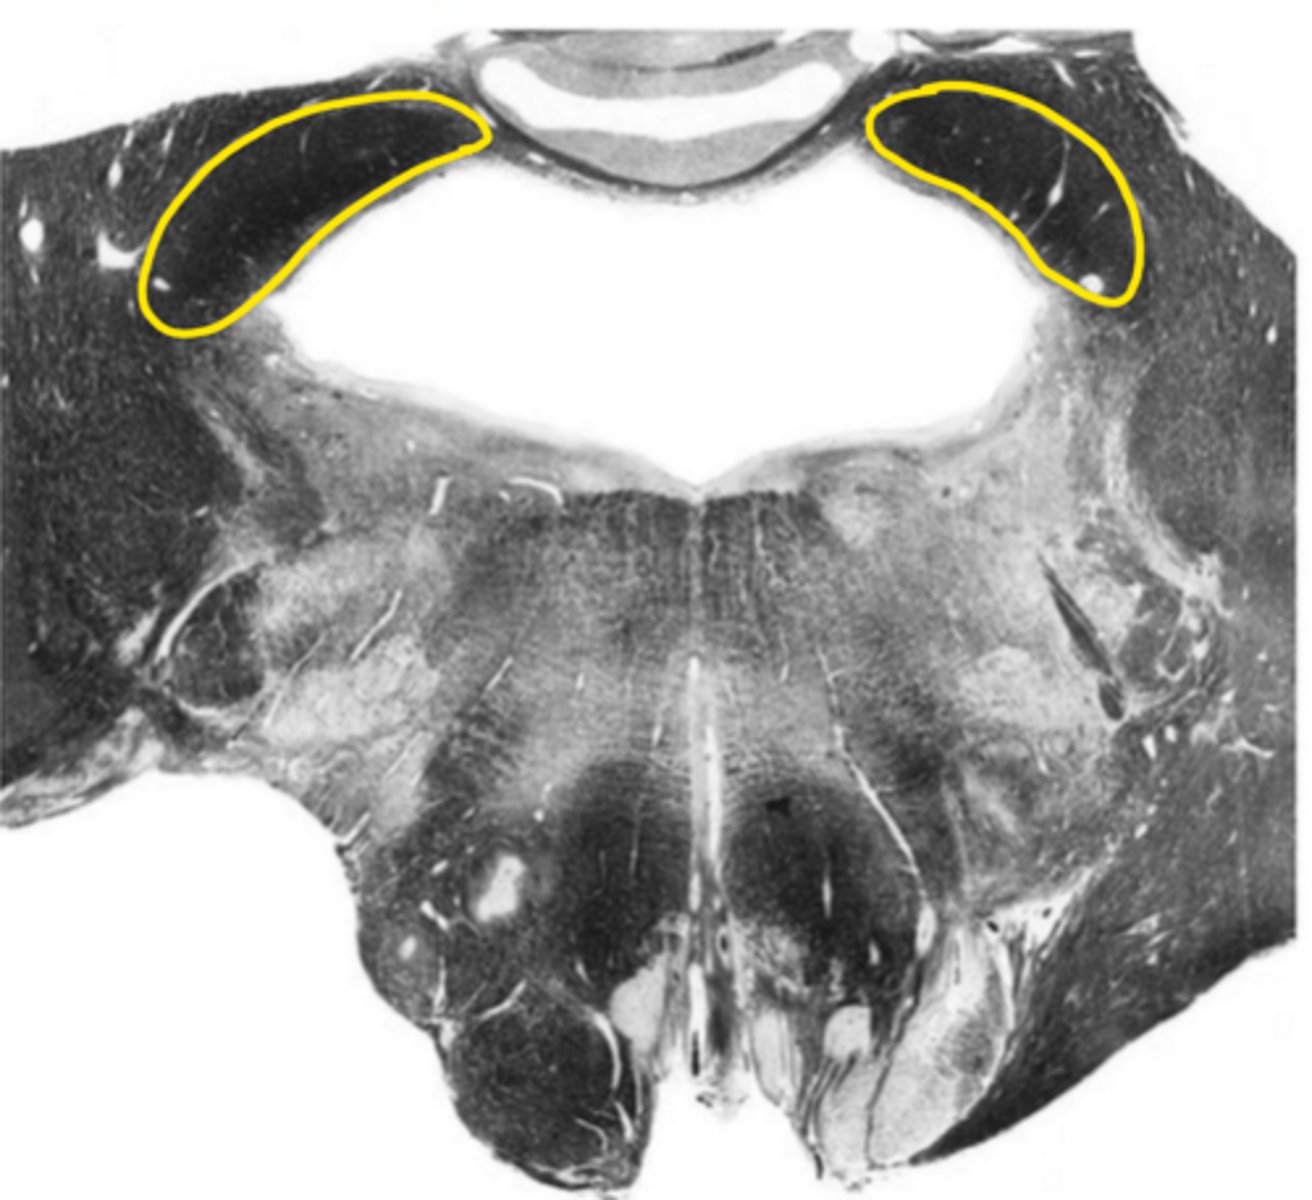

fourth ventricle

ID the space

hypoglossal nucleus

ID the nucleus

vestibular nucleus

inferior cerebellar peduncles

ID the structure

reticular formation

vagus nerve

ID the nerve

principle olivary nucleus

corticospinal fibers

hypoglossal nerve

medial lemniscus

anterior median sulcus